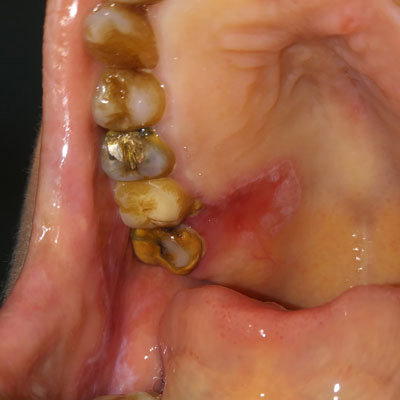

Red lesion